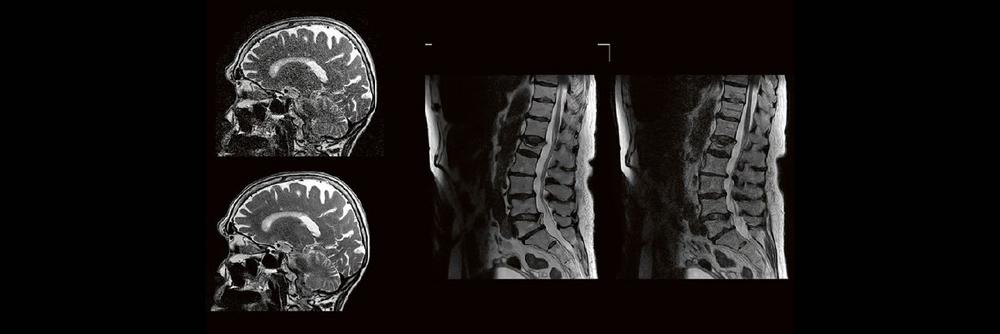

Künstliche Intelligenz spielt in der klinischen Anwendung eine immer größer werdende Rolle. Im radiologischen Sektor erfährt besonders die Magnetresonanztomographie aktuell einen regelrechten KI-Hype. Kürzere Untersuchungszeiten, eine höhere Bildqualität oder eine Kombination aus Zeit und Qualität sind theoretisch möglich, doch ist die KI in der Praxis mehr als eine Spielerei? Wie aufwendig ist es diese in den Alltag der Medizinischen Technologen und Technologinnen zu integrieren?

Die Künstliche Intelligenz (KI) revolutioniert die Radiologie und kann Ärzte dabei unterstützen, medizinische Bilder schnell und genau zu analysieren und helfen, Krankheiten frühzeitig zu diagnostizieren. Hierdurch soll die Effizienz und Genauigkeit der Diagnosen und die Qualität der Patientenversorgung verbessert werden. Anhand von Beispielen werden derzeitige Anwendungen der KI in der radiologischen Diagnostik dargestellt, Grenzen aufgezeigt und zukünftige Anwendungsgebiete beschrieben.